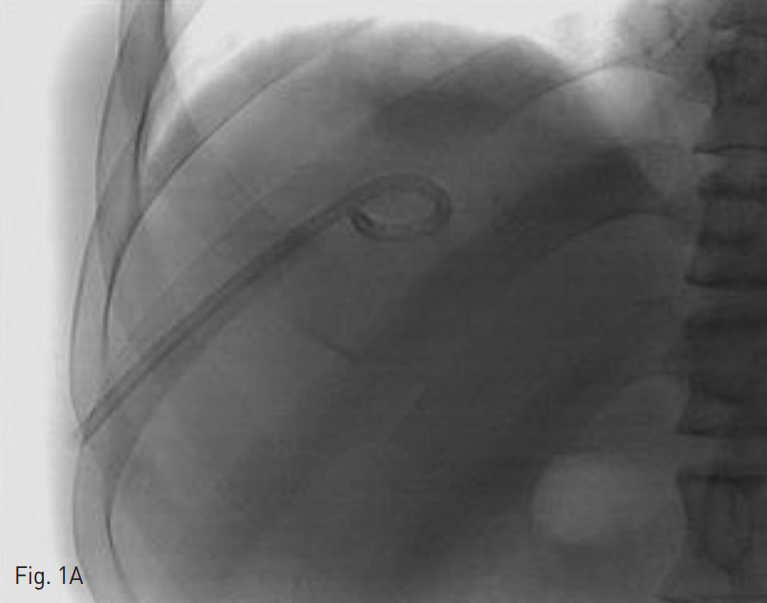

Fig. 1. A 65-year-old man who underwent pig-tail catheter insertion for the right hepatic abscess.

A. A fluoroscopic image before procedure shows accidental migration of pig-tail catheter fragment. The hub side of pig-tail catheter fragment is located in the catheter tract.